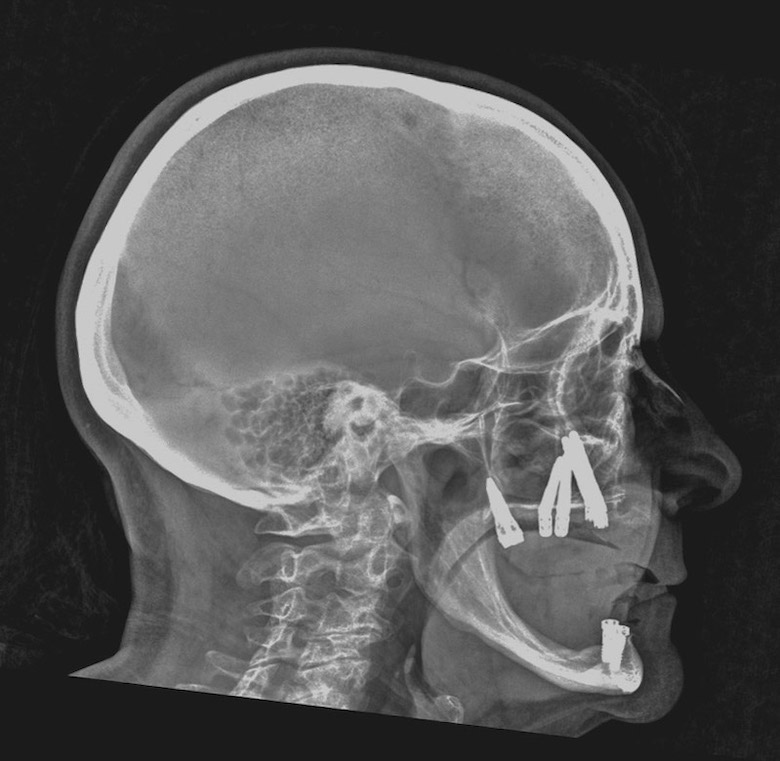

Restauración con implantes finalizada.

Mario Venturini, director del Instituto de Cirugía Maxilofacial en Rosario, Argentina, nos cuenta el tema que impartirá en la Jornada Virtual de Implantología de AIOI, que versará sobre “Implantología con anclaje extramaxilar”, técnica que permite reconstituir el arco dentario completo del paciente.

La implantología impulsó una mejora en la calidad de vida de los pacientes, mejorando notablemente no solo su confort y estética sino también su autoestima. Aunque pareciera poco y no lo es, evitó dañar más piezas dentarias para lograr un mismo resultado. Si todo ello es cierto, válido y genuino, el anclaje extramaxilar vino más aún, hace ya tiempo, a dar otro gran salto en la resolución quirúrgico protésica en un sesgo de pacientes que seguían excluidos de los beneficios de la implantología por razones obvias: carecían de stock óseo donde implantar.